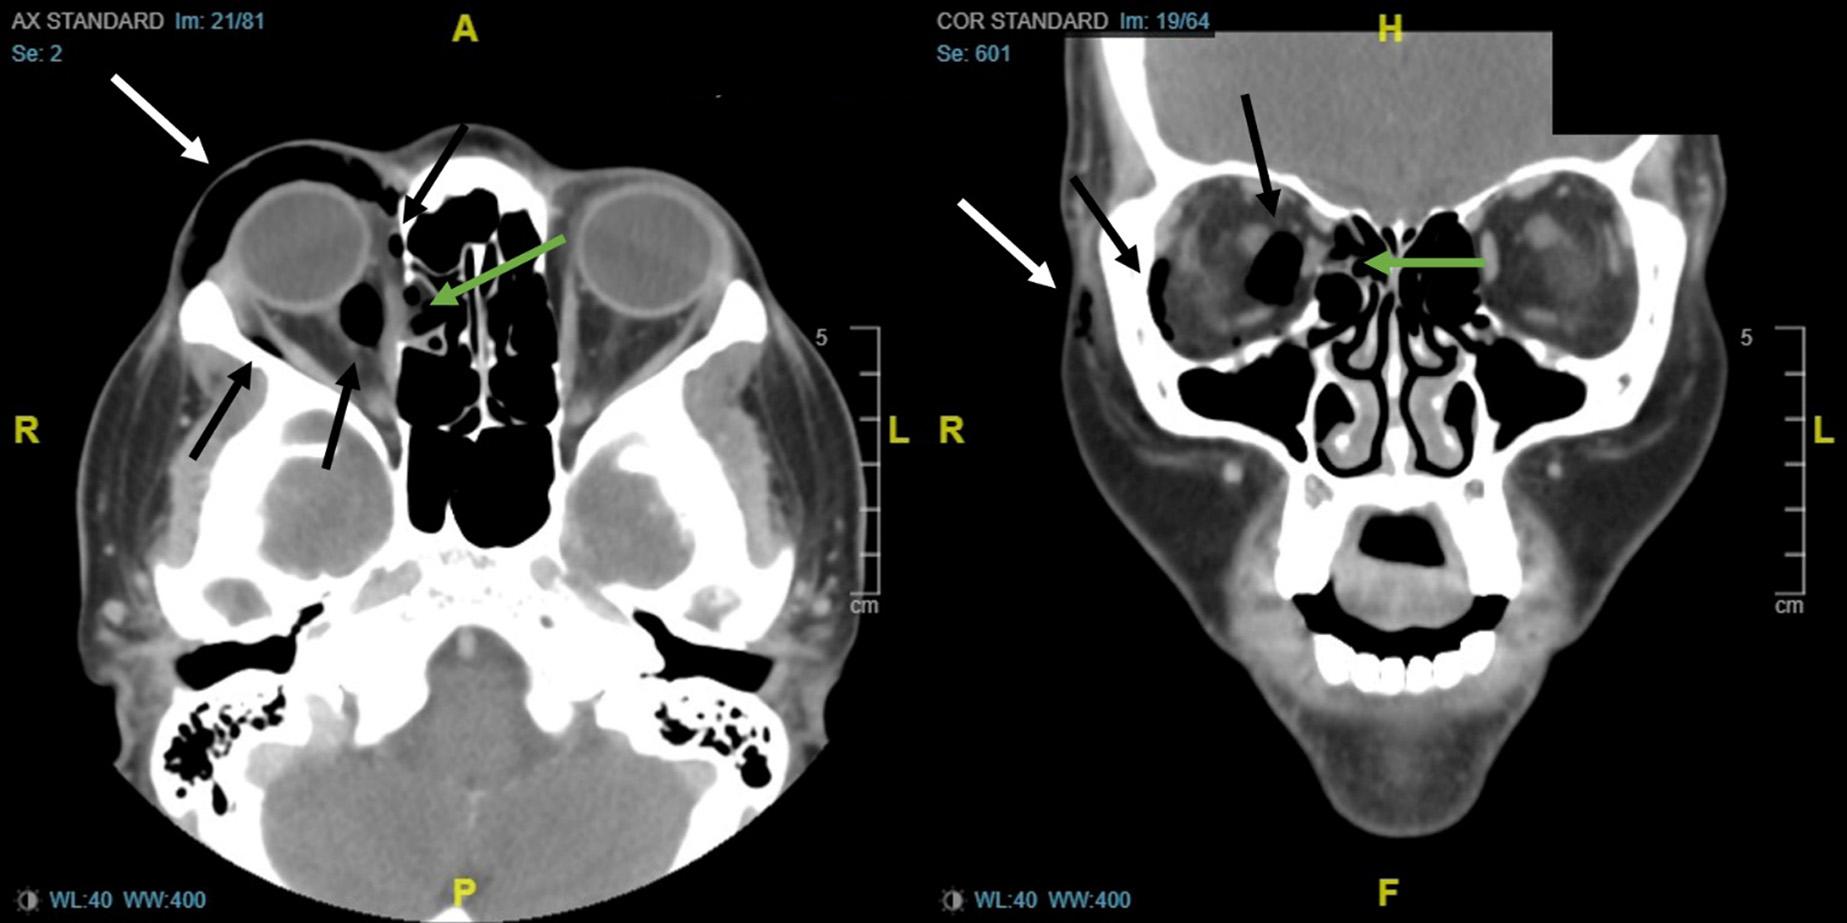

168 Atraumatic Orbital Emphysema in a Young Woman

Eladio Albornoz, Janet Wildemuth, Josephine Valenzuela